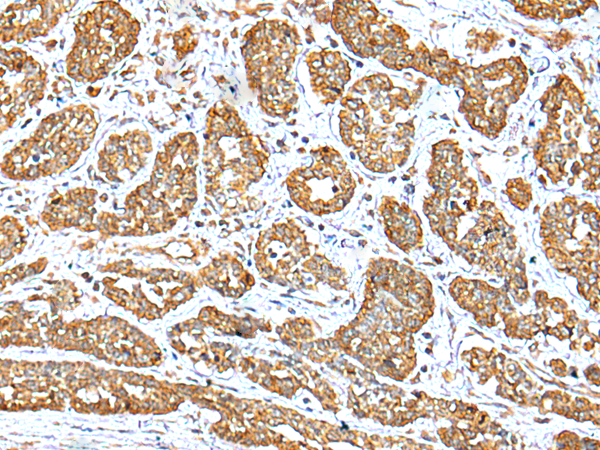

IHC positive control: |

Human breast cancer and human esophagus cancer |